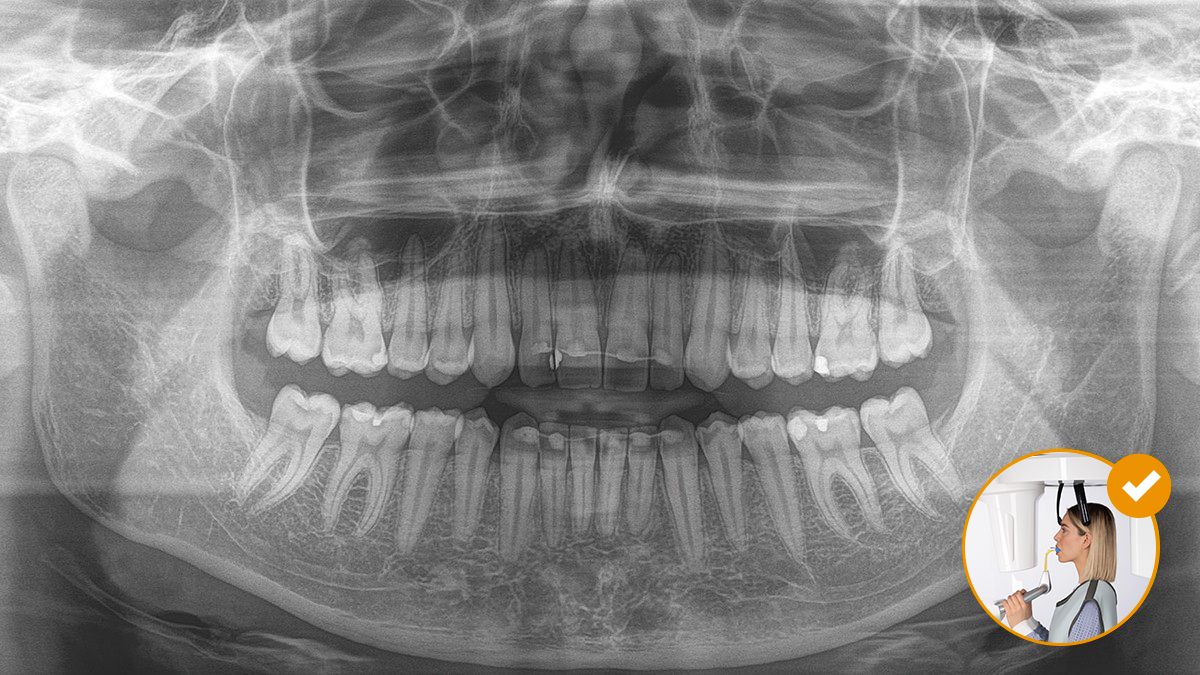

The operation of the occlusal bite block couldn't be simpler. With the help of the symbols and colours on the display of the X-ray device, practitioners have all the information required for optimal fine-tuning of the device. Illuminated arrows indicate in which direction the unit must be moved to achieve ideal head inclination. The device stops automatically once the correct position has been reached.

"Thanks to the Auto-Positioner, waiting times are reduced."

Dr. Stamnitz & Kollegen, Langen, Germany